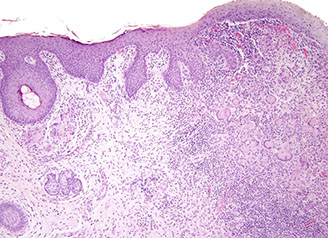

Ulcerative Colitis (UC)

Autoimmune dz c chronic destructiion of crypts presenting c periodic bloody diarrhea and no abdominal mass, MC in ~20 yo

- primarily based in mucosa c continuous rectal involvement affecting only superficial layers (mucosa and submucosa)

- pseudopolyps (appear so 2/2 loss of surrounding mucosa) freely hanging on mesentary, also see filiform (post-inflammatory) polyps at any stage; also inflammatory polys (seen when mound of normal mucosa in pseudopolyp protrudes and surrounding degenerated epithelium regenerates)

- endoscopically varies c degree of activity depending on several factors (tx, duration, severity), involving rectum and moving prox, making mucosa look bloody red that is friable and granular

- normal sub-mucosal vasculature lost, to endoscopist this is a clue for chronic colitis

- pt may lose haustral folds from repeat inflam

- generally confluent, but can have "skip" areas in cecum

- diffuse chronic duodenitis assoc c UC is predictor of pouchitis

- should start screening for cancer 8-10 yrs after dx of UC, in which multiple bx's are taken

Imaging: "Lead-pipe" appearance

Micro: architectural distortions (from repair) and inc chronic inflam (eos, lymphs, plasma cells)in mucosa characteristic; crypt abscesses (neuts in crypt lumen) and cryptitis (neuts in crypt epithelium), ulcers, bleeding, no granuloma formation

- regenerating glands don't have mucin or mature goblet cells and are immature

- lymph aggs seen at mucosal - submucosal interface

- although granulomas not common, can have granulomatous foreign body response (which is a granuloma, but causes confusion in reports) or mucin granulomas

- commonly see Paneth metaplasia, but not as much pyloric metaplasia

- usually not too much inflam in submucosa, and not transmural

-basal plasmacytosis seen in UC and Crohn

Complicated by toxic megacolon, colorectal ca (up to 10%), malnutrition, arthritis, uveitis

Extraintestinally can see pyoderma gangrenosum and primary sclerosing cholangitis (PSC) or Primary Biliary Cirrhosis (PBC)

Dx: (+) p-ANCA (70%), no specific tests avail

- should initially r/o bugs (shig, Salm, C jejuni, CMV etc)

- has Th2-like inflammation

DDx: Crohn dz (usually correlates c ASCA, not p-ANCA), long-standing infx (has more acute inflam in lamina propria, and less architectural distortion), medications (NSAIDS), chronic ischemic colitis (differentiate c pt age, location of inflam, inc muscularis propria inflam, and lack of acute inflam in epithelium)

Tx: 5-ASA preparations [sulfasalazine], steroid enema in acute dz; infliximab, colectomy

- azathioprine and 6-MP used to wean pts off roids

Px: If fatal, occurs in first 2 yrs of dz, and 2/2 fulminant dz (toxic colitis)

- long-standing inflam assoc c dysplasia and adenocarcinoma (need annual biopsies if have dz >8 yrs) which is usually left-sided, ulcerated or flat, and well to mod differentiated